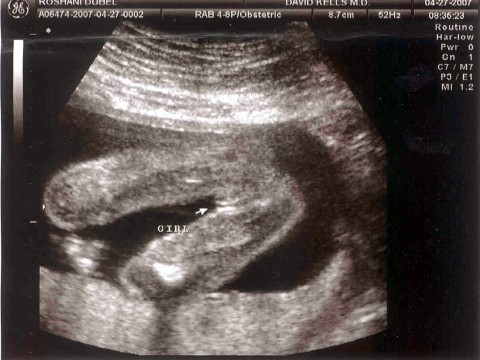

April 27, 2007

After years of longing and months of hoping and envying those who have,

I am happy to say that William and I are going to have a baby

girl. Although the ultrasound puts the baby's due date for

September 13, 2007, it is close to the due date the doctor suggested

that no change was made to it. Therefore, the due date remains at

September 09, 2007. My prediction, given my history and if all

things go well, the baby will be born mid to late August. I'm so

excited! And yes, we do have a name for the baby. William

and I are

just working on how we want it spelled.

IT'S A GIRL!!!!